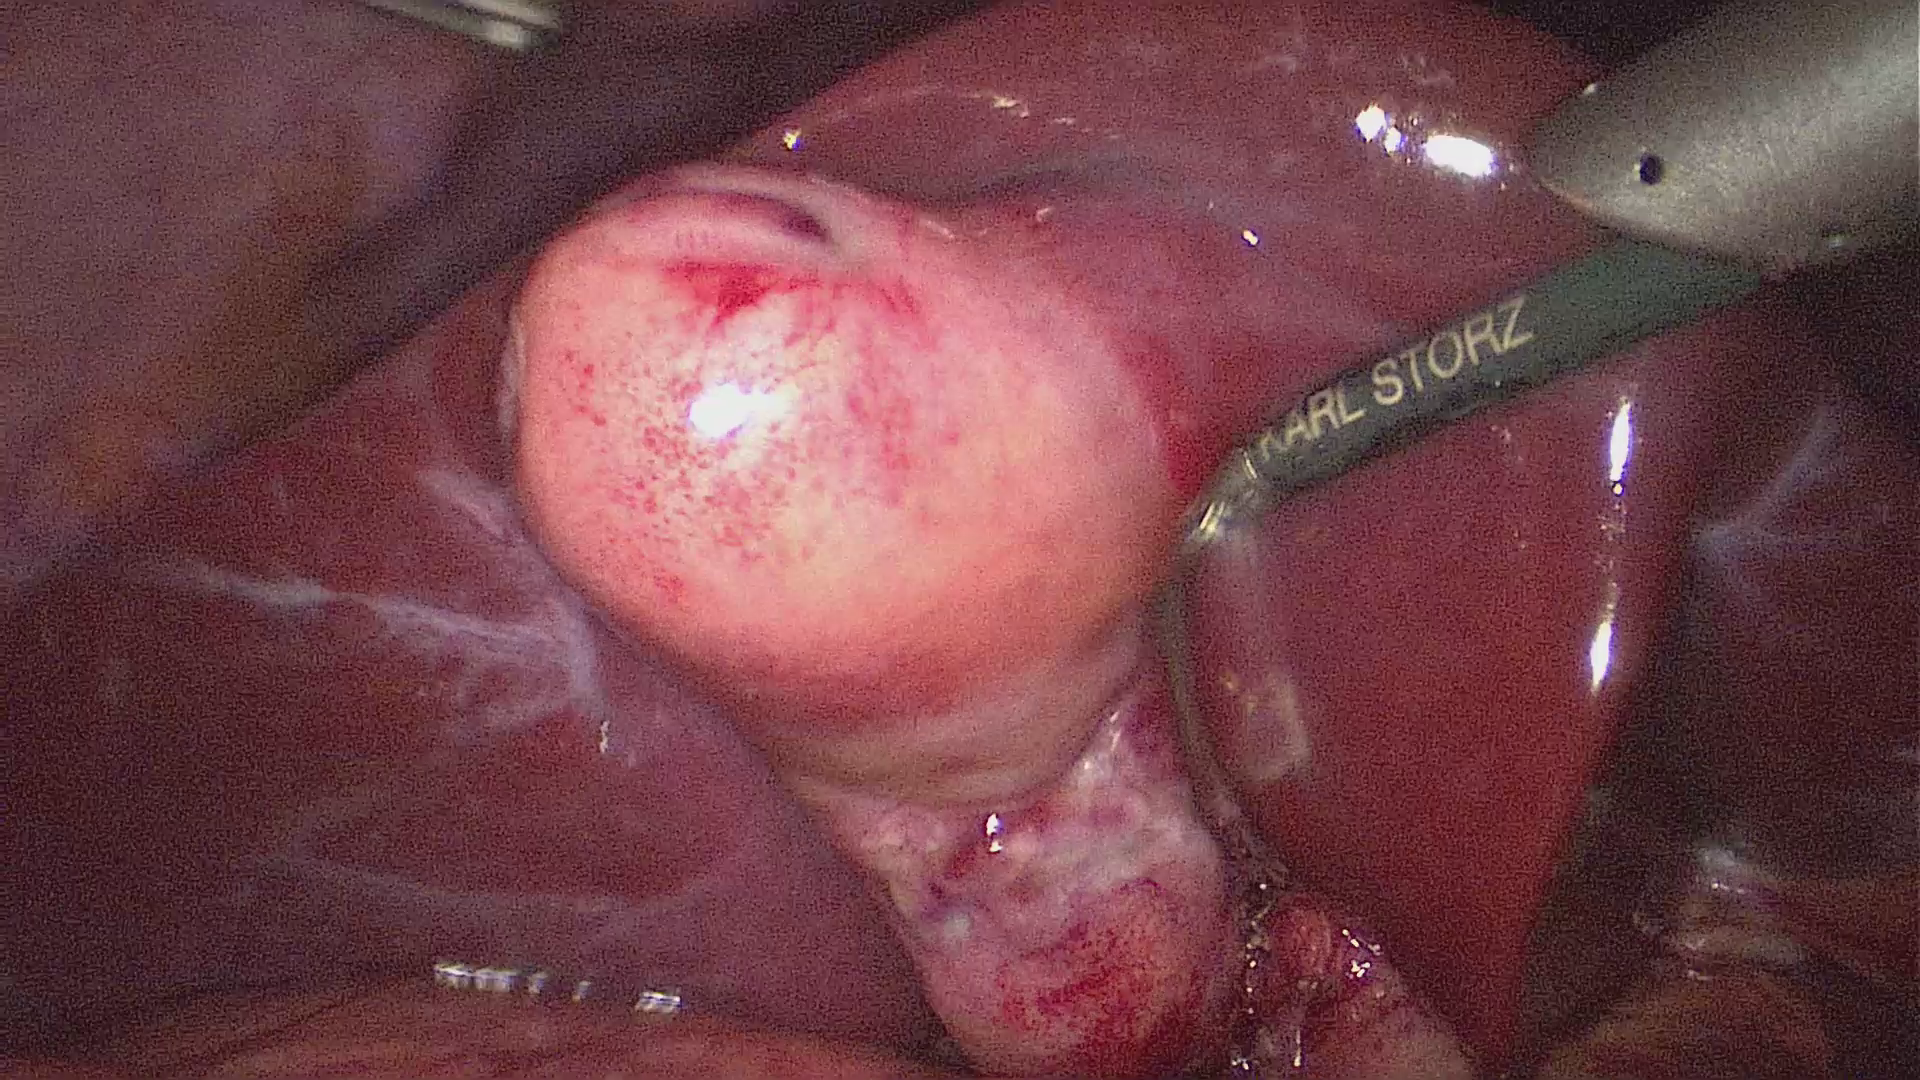

Πολύποδες

Οι νεανικοί πολύποδες αποτελούν το 80% των πολυπόδων που εμφανίζονται στα παιδιά. Έχουν σφαιρικό σχήμα και έχουν μίσχο. Δεν είναι κακοήθεις. Εμφανίζονται συνήθως σε παιδιά ηλικίας 3-10 ετών, με μέγιστο τα 5-6 έτη. Το 85% των παιδιών έχουν ένα μόνο πολύποδα.